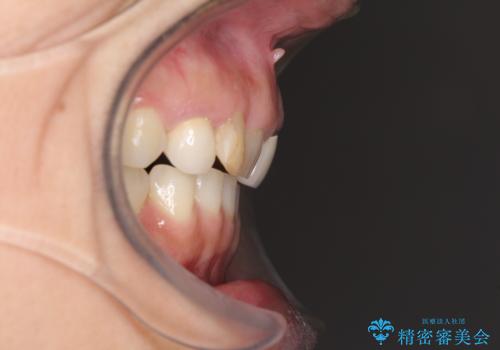

診察したところ、上顎前歯に過剰歯があることで上顎歯列が大きくなり、上下の歯が奥歯の一部でしか咬み合っていない状態でした。

上下非接触の咬み合わせは、舌突出癖によるところが大きく、トレーニングを行いながら治療を進めていきました。

なかなか突出癖が改善できず、過剰歯を抜歯したスペースを閉じるまでに時間がかかりました。